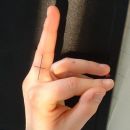

Finger

Lagerung

sitzend - seitlich zum Tisch

1. Möglichkeit - d.-v.

abgewinkelter Unterarm liegt auf

die Hand steht senkrecht auf Kleinfingerseite

Daumen parallel u. überlagerungsfrei zum Bildempfänger stellen

2. Möglichkeit - v.-d.

Arm ausgestreckt Handinnenfläche zeigt nach oben

dabei Daumen parallel zum Bildempfänger drehen

3. Möglichkeit

Arm gewinkelt, in Kopfhöhe, Hand liegt dorsalwärts mit 45° auf der Kassette, D1 ist somit parallel zur Kassette (als Bettaufnahme oder am Stativ).